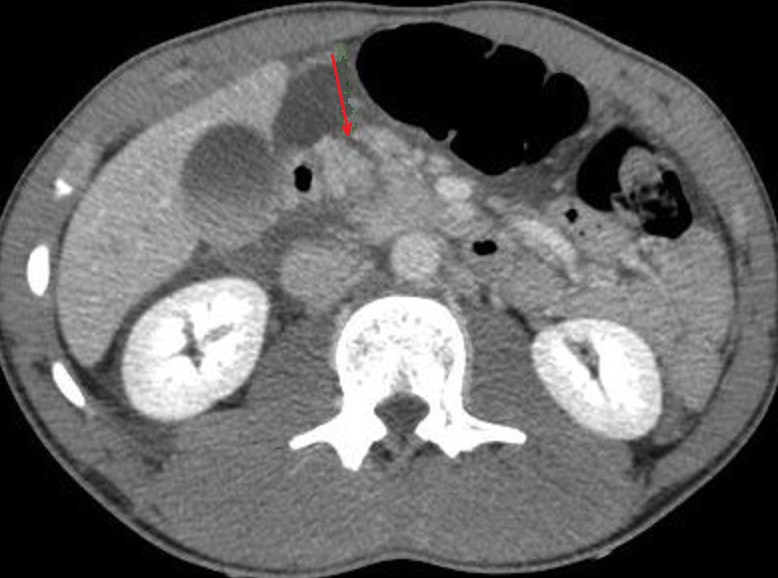

Image radiologique TDM de

contusion de la tete du pancreas avec de

elargir , heterogene a hypodense du pancreas avec un

epanchement liquidien peri-pre pancreatique ( fleche

rouge }. Coupe axiale TDM |

|

Un autre cas de trauma important du

pancreas avec image de transection totale de la tete

du pancreas . Epanchement peri , pre-pancreatique

peut en s'observer encore . Image radiologique

TDM du pancreas , coupe axiale |